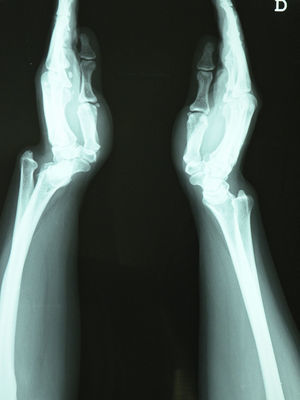

En el estudio radiográfico de muñecas en proyección PA (fig. 2), se evidenció en el carpo derecho los hallazgos típicos de la deformidad de Madelung1: acortamiento del radio en relación con el cúbito, radio curvado con convexidad dorsal y radial, angulación similar de la superficie articular radial distal, incongruencia de la articulación radiocubital distal y subluxación del carpo. En la proyección lateral (fig. 3), se apreciaba arqueamiento anterior del radio y subluxación dorsal de la cabeza cubital; el carpo también se encontraba subluxado cubital y palmarmente en la articulación radiocubital distal, de modo que los huesos del carpo parecían seguir al arqueamiento del radio2. Con el diagnóstico de síndrome del túnel carpiano bilateral secundario a deformidad de Madelung, se planteó derivación a Traumatología para cirugía. Debido a la demora de más de 2 meses, se propuso tratamiento médico con infiltraciones locales de corticosteroides. Se infiltró 1ml de triamcinolona en el carpo derecho, según técnica estándar3. El dolor comenzó a remitir a partir de los 2 días siguientes a la infiltración (EVA: 50/100), desapareciendo completamente el dolor en la revisión a la semana (EVA: 0/100).